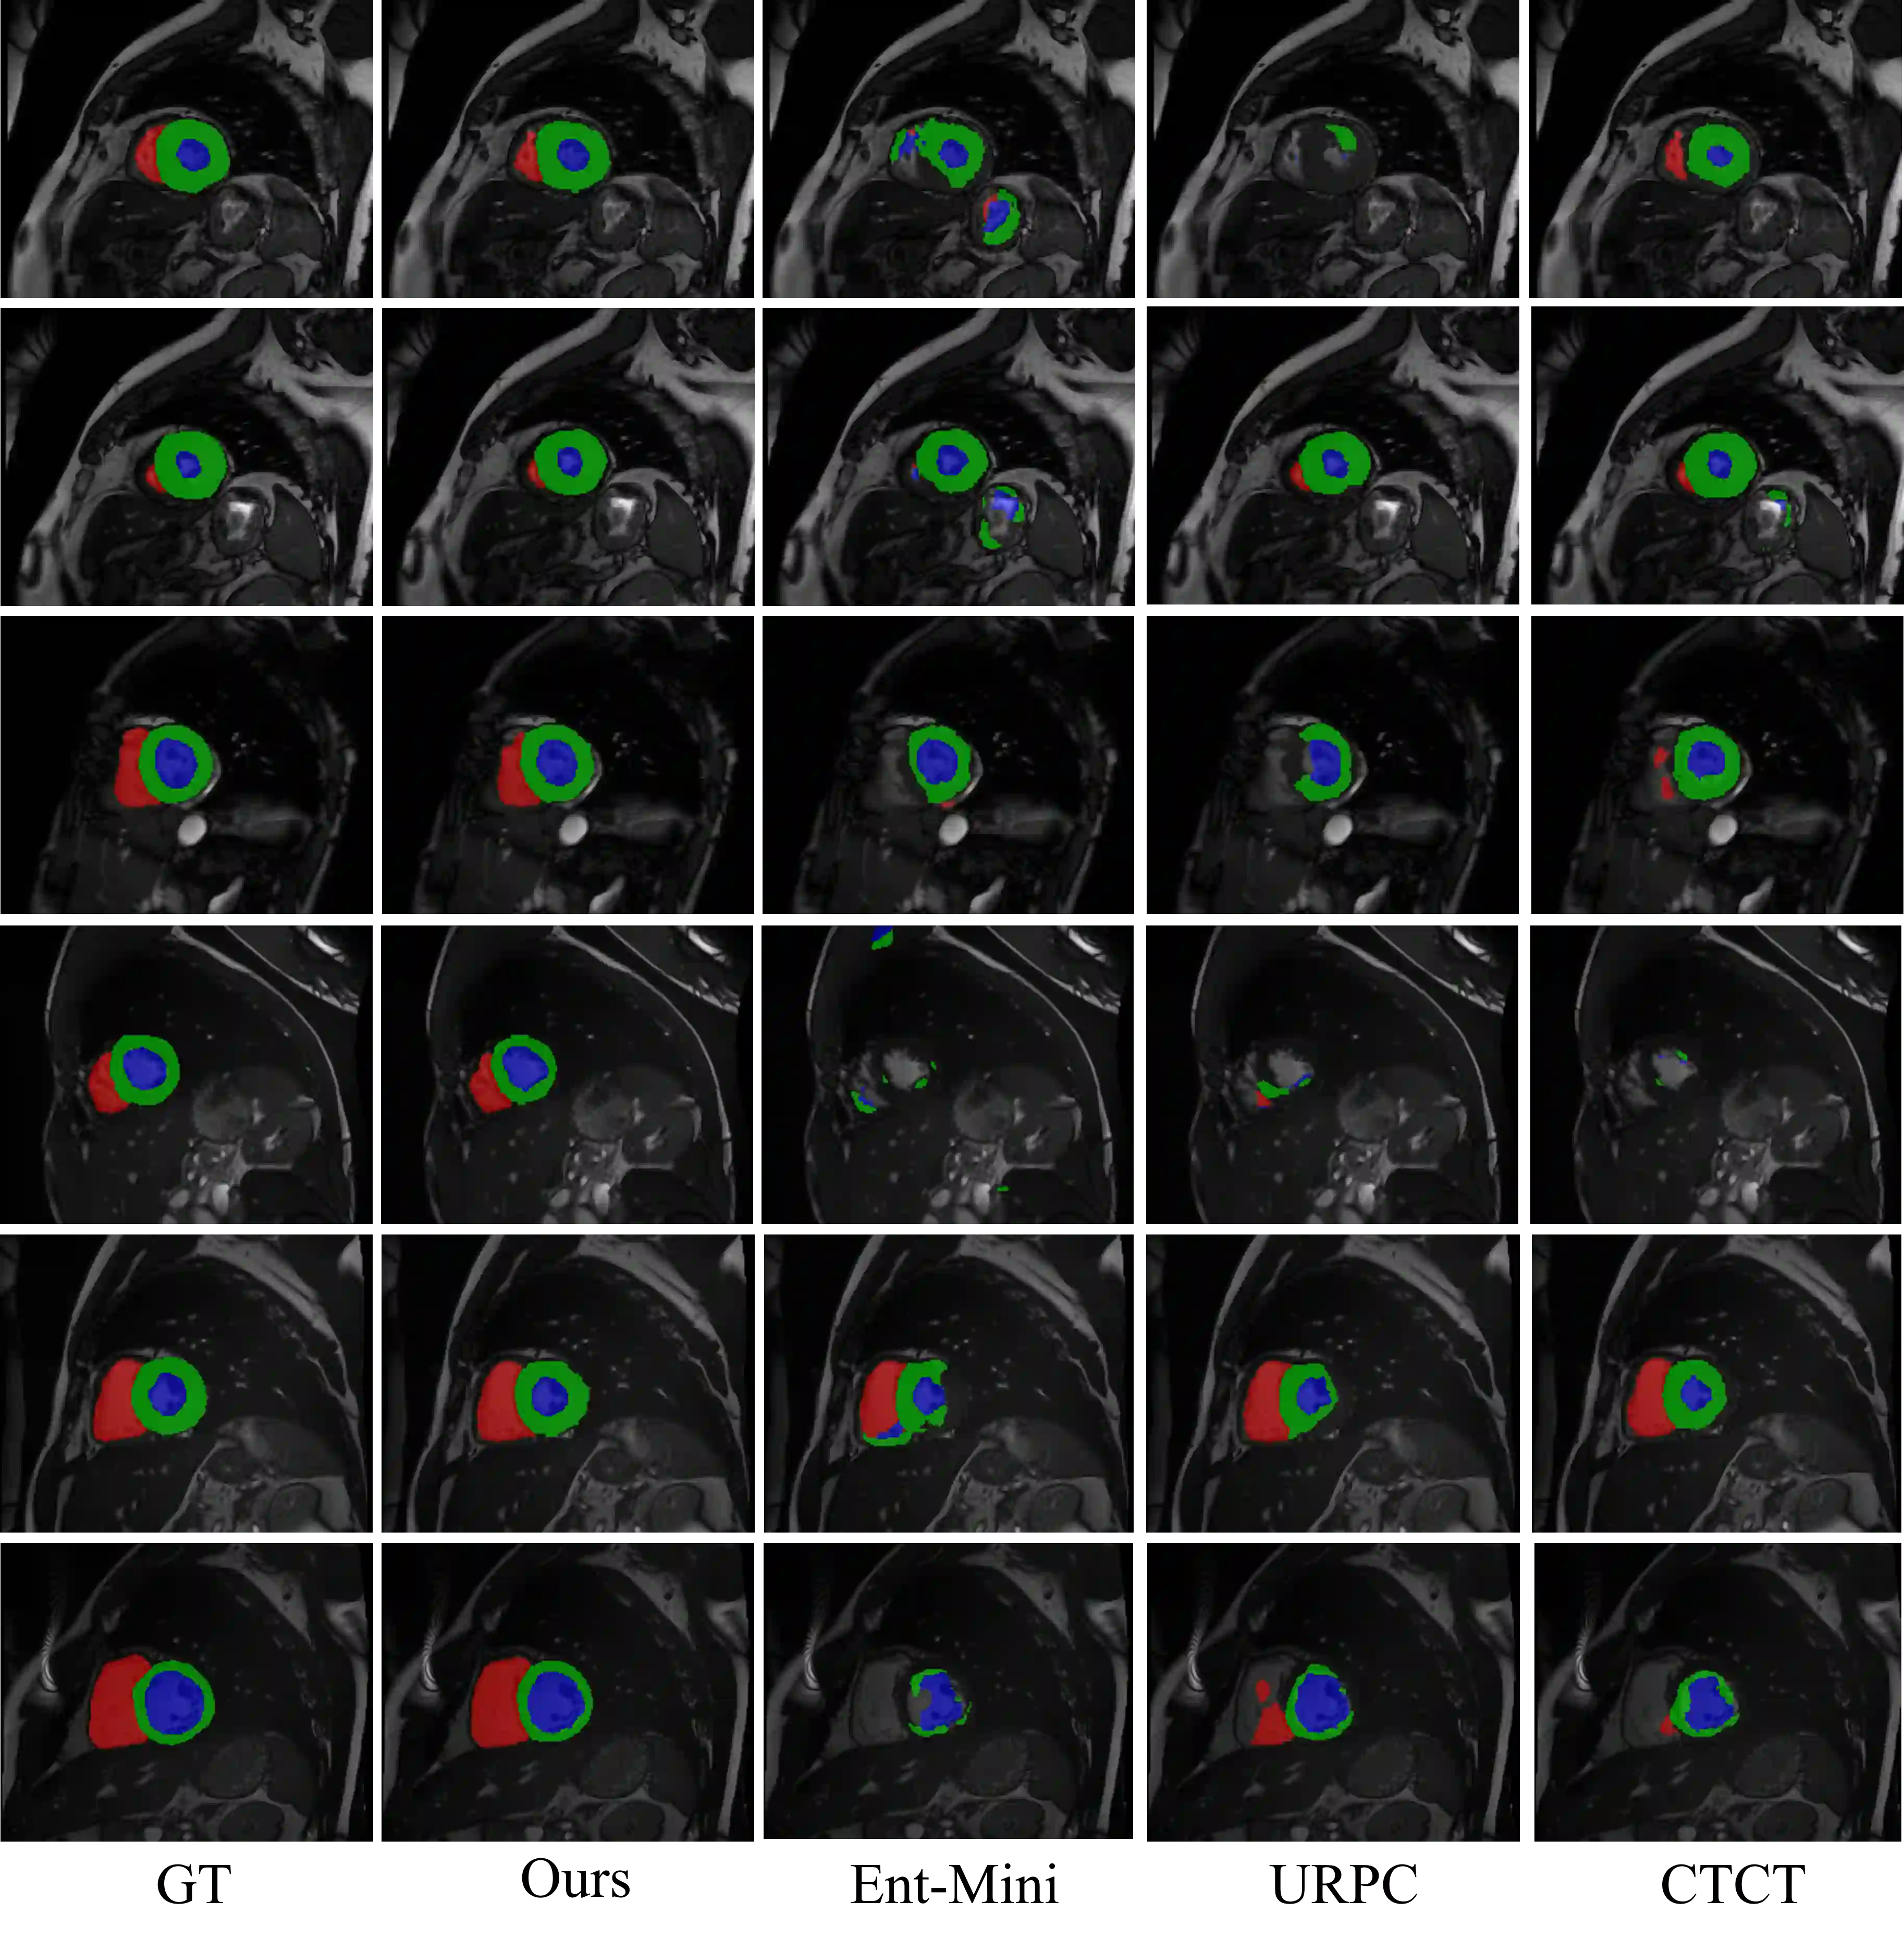

Semi-supervised medical image segmentation has attracted much attention in recent years because of the high cost of medical image annotations. In this paper, we propose a novel Inherent Consistent Learning (ICL) method, which aims to learn robust semantic category representations through the semantic consistency guidance of labeled and unlabeled data to help segmentation. In practice, we introduce two external modules namely Supervised Semantic Proxy Adaptor (SSPA) and Unsupervised Semantic Consistent Learner (USCL) that based on the attention mechanism to align the semantic category representations of labeled and unlabeled data, as well as update the global semantic representations over the entire training set. The proposed ICL is a plug-and-play scheme for various network architectures and the two modules are not involved in the testing stage. Experimental results on three public benchmarks show that the proposed method can outperform the state-of-the-art especially when the number of annotated data is extremely limited. Code is available at: https://github.com/zhuye98/ICL.git.